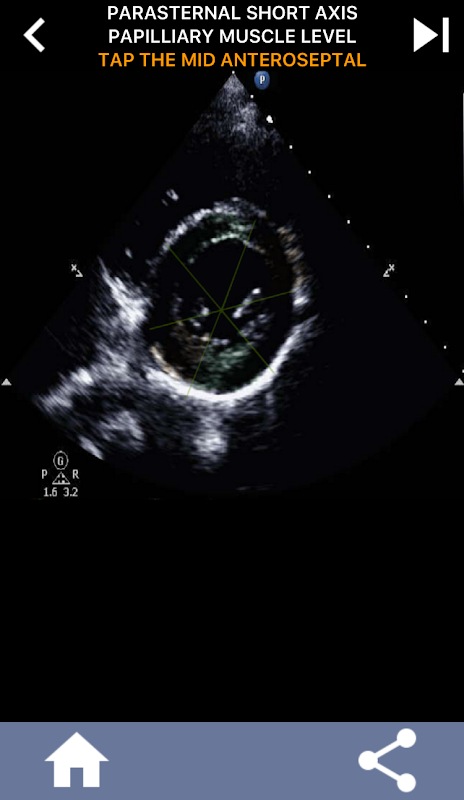

Quiz-based visual approach to learning the AHA heart segments: Echocardiography

Understanding the AHA (American Heart Association) heart segments is of utmost importance for a cardiac sonographer to effectively communicate with the cardiologist who writes the report. By knowing the specific anatomical regions and their corresponding segments, the sonographer can accurately describe and communicate any abnormalities or findings, ensuring clear and concise communication between both professionals.

This understanding becomes particularly crucial when the cardiologist seeks to ascertain the precise location of a problem or when the on-call physician identifies an issue within a specific region, prompting the sonographer to accurately display the corresponding segment, such as the mid-inferior wall. Thus, possessing a comprehensive grasp of the AHA heart segments is essential skill set.

This app will test your knowlegde using actual echo images, which I often find to be the best teaching method.